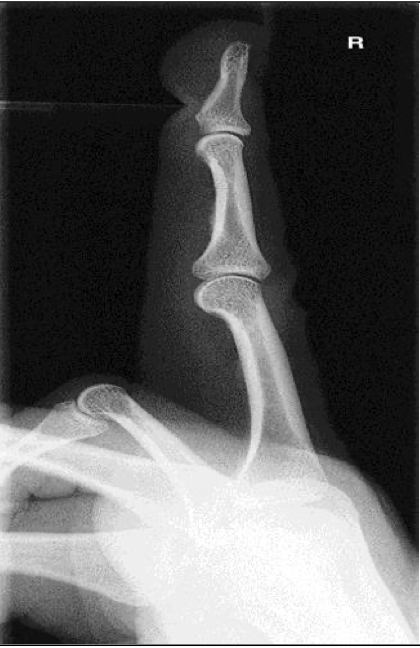

Lateromedial or Mediolateral- Finger ( 2nd-5th Digit)

Evaluation Criteria for Lateral Finger

• Entire finger and MCP joint demonstrated

• CR centered at PIP

• Collimation includes entire finger and at least MCP joint

• True lateral position

Anterior aspect is concave

Posterior aspect is straight or slightly convex

• Digit parallel to IR

IP and MP joints are open spaces